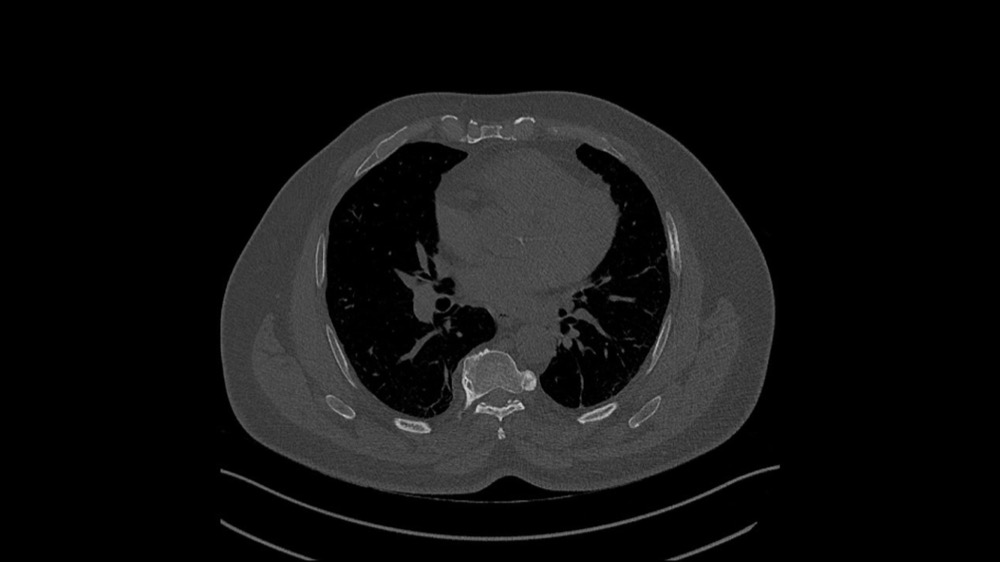

Marcilhacy / Dion / Kirchner / Oufighou / Tordjman 11/01/2023